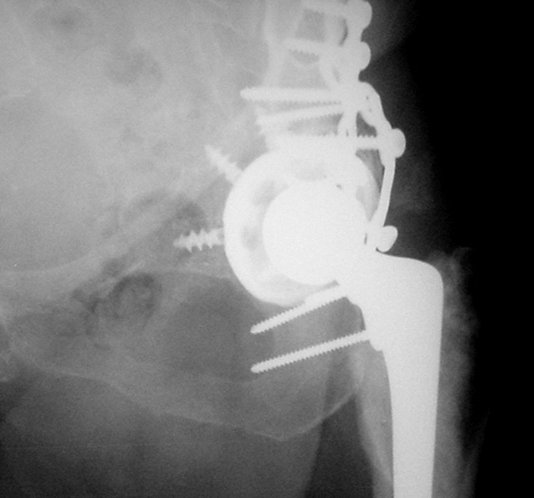

We do not have all information's, like: Judet views, CT, approach used at the time of total hip arthroplasty... what would help, but in general, I would do similar as it is presented with this 75 years old lady:

1. Dislocation of prosthesis

2. Removal of prosthesis head

3. Removal of the cup:we have available some nice, round cutters causing minimal damage of surrounding bone

4. Fix the acetabular fracture (fracture seems to be transverse type!?; it is a real fun to do it with femoral head removed)

5. New metal back cup with multiple holes for screws - improves

osteosynthesis

6. New poly insert and reduction.

As you know, in general, if prosthesis is not loose (and from the x-ray cup seems to be well fixed), we do not have to replace it.

1. Problem is that would be very hard to provide good stability - good job fixing the fracture with cup in place, although, of course,it is possible.

2. My preference would be to remove the cup. Having excellent view, approach to the acetabulum and good fixation can be accomplished (this has to be the premice, fracture well fixed before the cup in order to put in it); now, if you use the metal cup with multiple holes, it does work like nice plate and additional fixation to the fracture. If the cup is coated with hydroxy appatite, that will make healing and incorporation even better.

Установлена RM-чашка бесцементная,ножка тип Цвайммюллер производства Мathys,сделана костная пластика.В настоящее время необходим остеосинтез реконструктивной пластиной без удаления чашки,так как чашка стабильна.